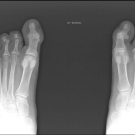

Jak PsA

Many patients with PsA cannot achieve comprehensive control of their symptoms, despite a variety of available treatments. Learn more about an available JAK inhibitor along with findings from the two phase 3...